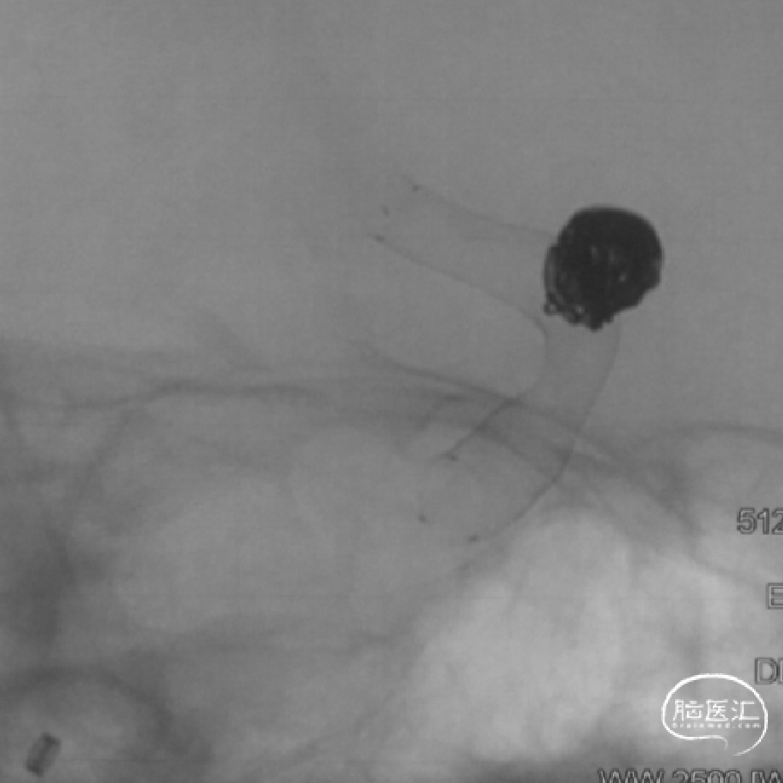

载瘤动脉近端直径4.24mm,远端直径3.05mm,选择通桥麒麟™血流导向密网支架 TQL-40-45。

微导丝囊内成绊,超选到大脑中动脉M1远端。

撤出微导丝,送入弹簧圈微导管至瘤腔内。

固定输送系统,回撤微导管,逐步释放通桥麒麟™血流导向密网支架头端,至头端张开为V型。

继续送入弹簧圈填塞。

再次造影确认打开情况,用微导丝继续按摩支架尾端。